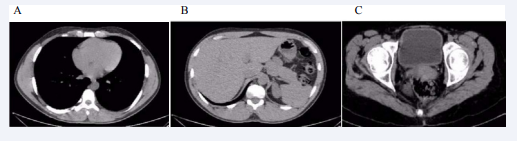

Histopathological report of the lesion revealed for first case was heterologous cervical adenosarcoma with rhabdomyoblastic and chondroid differentiation, without myometrial and lymphovascular invasion. The second case was adenosarcoma with ulcerated polypoid cervical tumor without sarcomatous overgrowth, no rhabdomyoblastic and no chondroid differentiation, without myometrial and lymphovascular invasion (Figure 2).

Figure 2 Histopathological examination evidencing müllerianadenosarcoma of the cervix. (Images obtained from the presented cases)

Figure 2 Histopathological examination evidencing müllerianadenosarcoma of the cervix. (Images obtained from the presented cases).